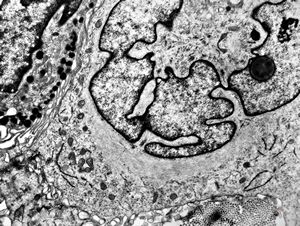

F, 36y. | Sézary-like cell - generalized eruptive histiocytoma

F, 36y. | generalized eruptive histiocytoma - cerebriform nucleus - Sezary cell